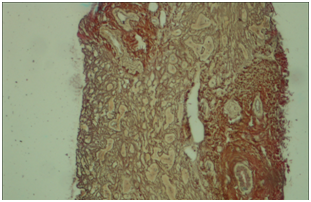

Finally, liver biopsy was done .The sample was stained with Hematoxylin, and Eosin, Trichrome and Reticulin. Extensive lobular architecture disarray with marked necro-inflammatory changes of parenchyma characterized by obvious hydropic changes and single cell necrosis of hepatocytes as well as infiltration of mixed inflammatory cells was shown in Hematoxylin, and Eosin staining (Figure 2). Collapse of reticulin network associated with psuedolobule formation as well as portal fibrosis was shown in Reticulin and Masson-Trichrome staining (Figures 3&4). Overall findings were in favour of an acute/sub acute liver injury according to Modified HAI score grade: 14/18, stage: 3/6.

Figure 2 (Hematoxylin and Eosin X400) Hydropic changes and single cell necrosis of hepatocytes as well as infiltration of mixed inflammatory cells.